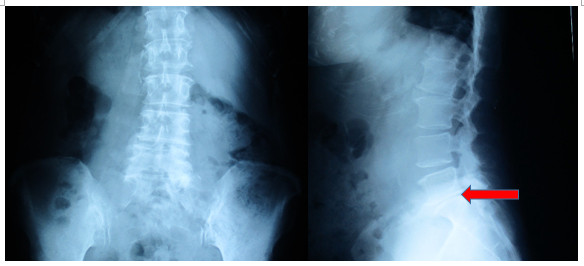

71歲的張女士是一位退休人士,酷愛行山攝影,近幾個月發現左腳疼痛及麻痺,症狀是稍

微長時間走路左腳便無力及麻痺,左邊盆骨位置隱隱作痛。從醫生幫她拍的X光可以看見腰椎側彎,盆骨稍微一高一低,整條腰椎骨退化,腰椎第五節骶骨第一節空間收窄,判斷為腰椎五節椎間盤突出及盆骨錯位,但做了多次糾正盆骨治療都沒有太大改善!

圖左:從X光看見個案二患者腰椎側彎,盆骨稍微一高一低;圖右:腰椎第五節骶骨第一節空間收窄。